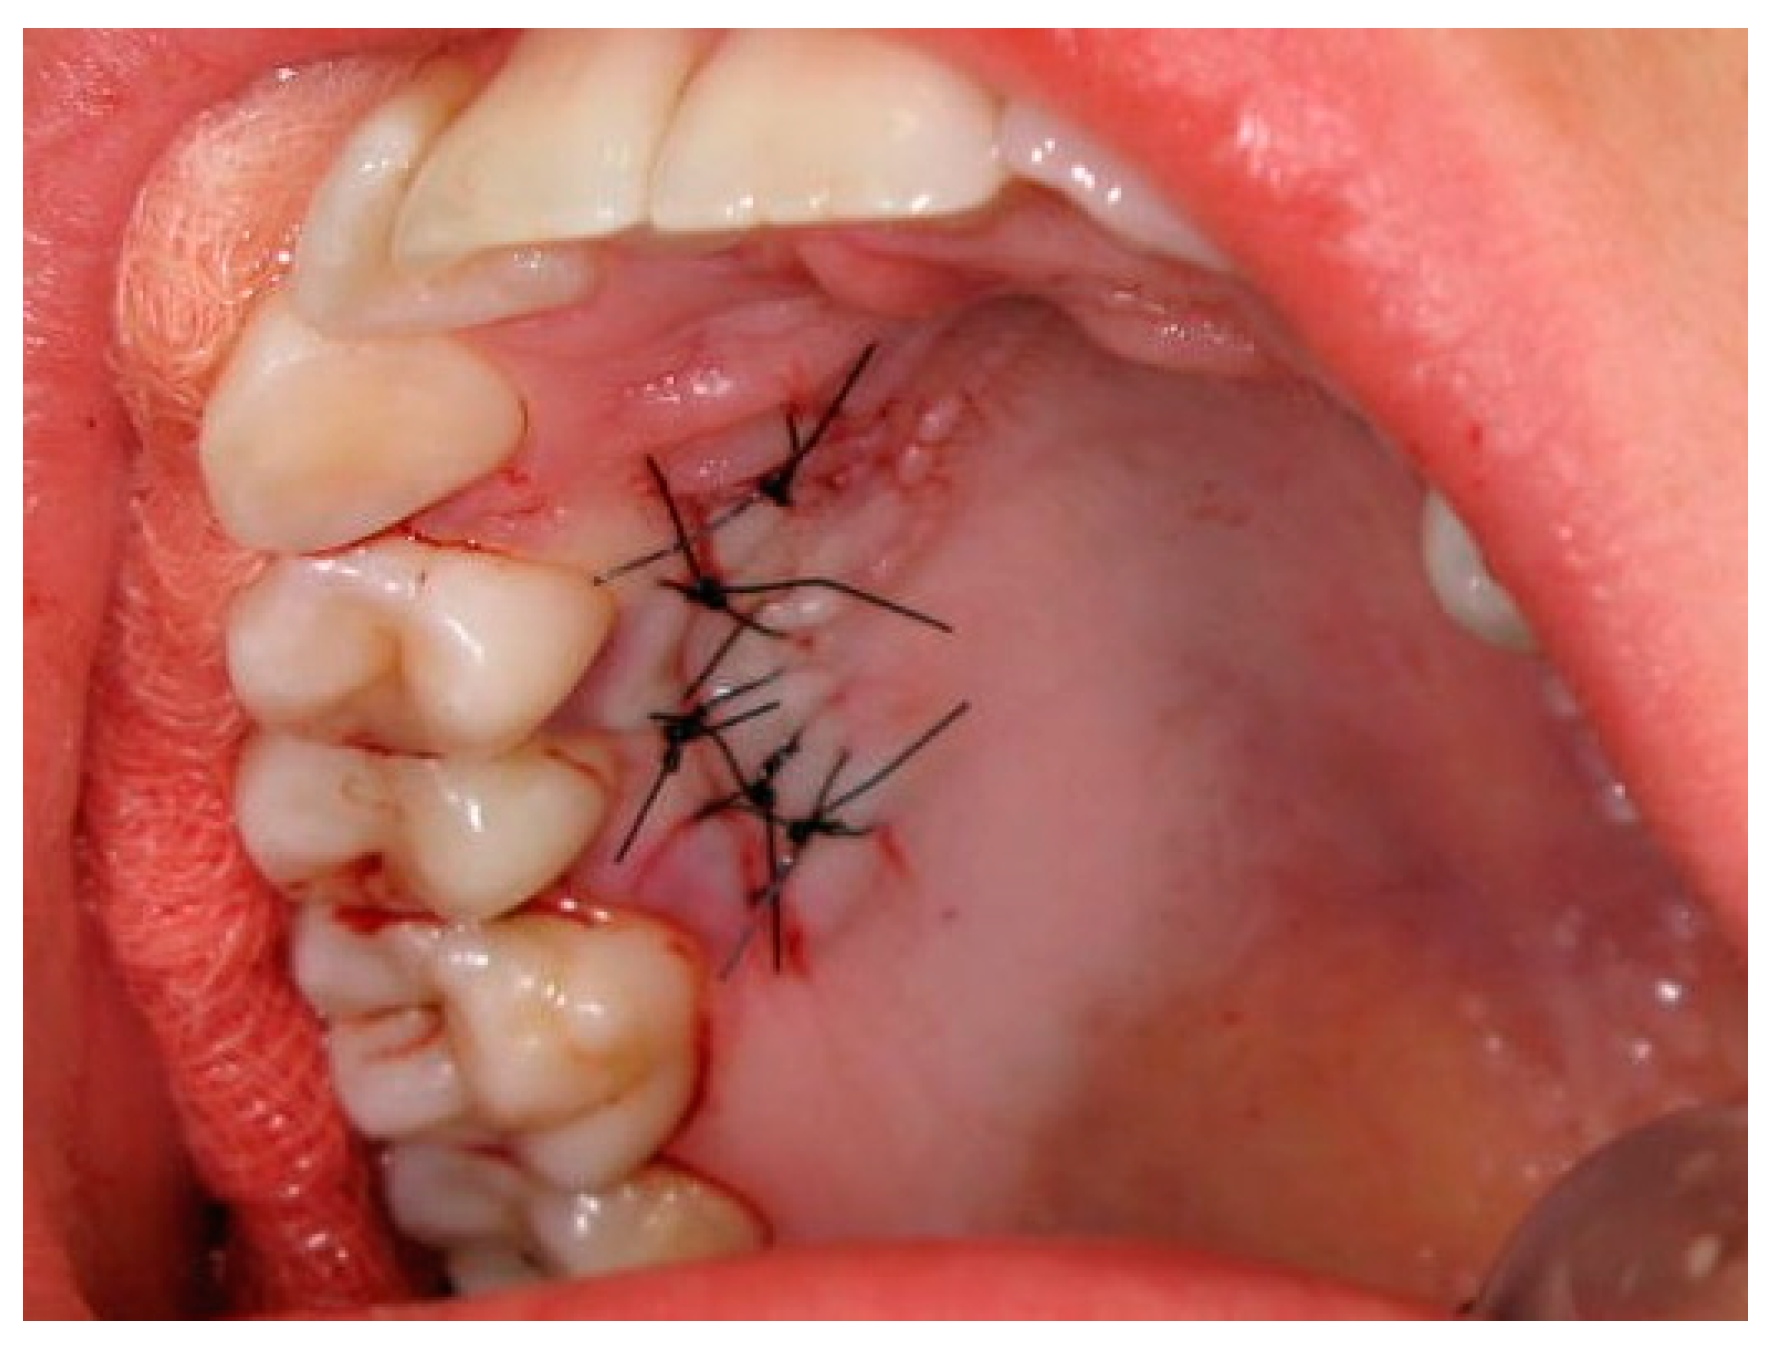

:1. Introduction

2. Materials and Methods

2.3. Surgical Procedures